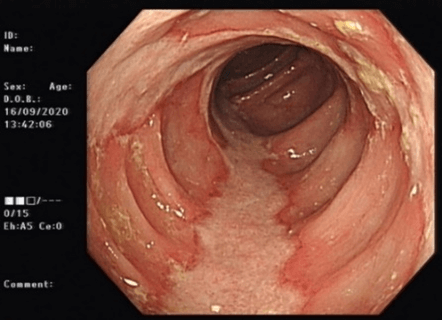

CT abdomen and pelvis with contrast showed non-specific colitis of the descending colon. Coronal and axial cuts are shown in (Figures 3 & 4). Following this, he underwent a sigmoidoscopy that showed a large mass-like ulcerated lesion in the descending colon. This involved about 15 cm of the colon and occupied about 30% of the lumen, as shown in (Figure 1). Histology was suggestive of ischaemic colitis (Figures 5-8). The multidisciplinary meeting recommended an interval colonoscopy which showed resolution of the colonic mass lesion (Figure 2). He was fluid resuscitated and started on empiric broad-spectrum antibiotics.

Figure 2: Endoscopic findings at interval colonoscopy.

The differential diagnosis in these patients includes inflammatory bowel disease, acute diverticulitis, infectious colitis, solitary rectal ulcer syndrome and colorectal carcinoma. Significantly, the endoscopic features of ischaemic colitis can mimic those of colorectal carcinoma, with more extensive inflammatory masses/ulcerations appearing as neoplastic. There are multiple case reports in the literature of similar endoscopic presentations and subsequent endoscopic and histological outcomes [9, 11, 12]. This case is of particular interest because of a descending colonic mass lesion, which turned out not to be malignant.